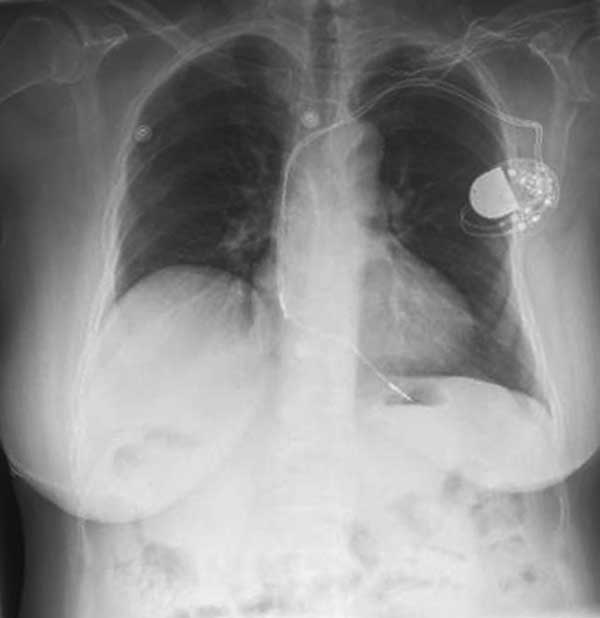

Atrioventricular (AV) block occurs when electrical conduction is impaired between the heart’s four chambers, most often by fibrosis or sclerosis. It can result in passing out, severe fatigue and death. The only current therapy is to place a pacemaker.

An estimated 3 million people worldwide have pacemakers, and 600,000 pacemakers are implanted annually. But while a common treatment and low-risk procedure, it can result in serious complications. Generator charges also carry a high risk of infection in and around the heart. However, there has been limited research on whether behavioral modifications can prevent heart block and which ethnicities are most at risk.